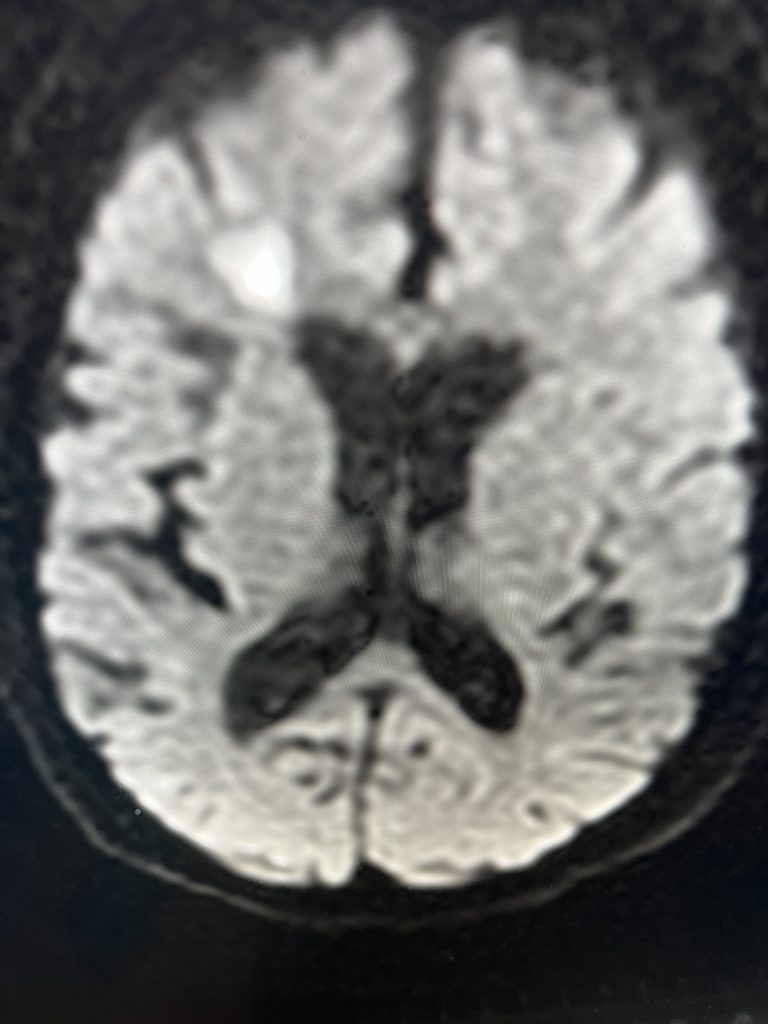

Central Cord Syndrome

Author: Yusef Imani M.D., F.A.A.N.S., Read More!